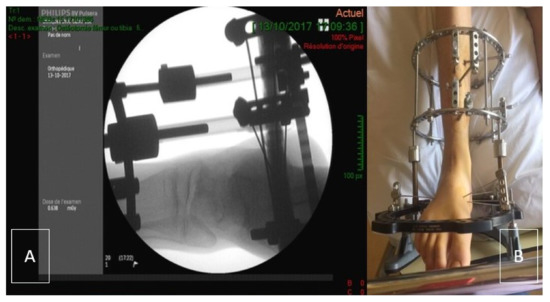

Figure 1. (A) Per-operative evaluation of Ilizarov placement using X-ray. (B) Clinical picture of the Ilizarov frame (post-surgical status-day 1).

Ankle joint distraction can be a good alternative to spare the joint. Distraction arthroplasty does not use any graft material. This procedure employs an external fixator which crosses the ankle joint and applies a distraction force across the tibio-talar articulation (Figure 1) [6]. The theory behind distraction arthroplasty is that it allows for the reparative potential of the joint by removing mechanical stress. Ankle joint distraction has recently been used to treat three young patients with hemophilic arthropathy of the ankle, achieving clinical and radiological improvement at short-term follow-up, with no significant blood loss [7]. The authors considered this application justified by the noteworthy clinical outcomes of previous studies in ankle osteoarthritis. In a work by Ploegmaker et al., joint distraction achieved good and durable clinical results (73% of the cases) in post-traumatic ankle osteoarthritis at a minimum follow-up of seven years [8]. Distraction arthroplasty appears therefore to be a reasonable option to provide a good percentage of patients a satisfactory period of time of improvement, less invasive than “traditional” cartilage repair procedures using autograft or allograft.

Approximately 12 weeks after the collapse of the talar dome was observed on MRI, the patient underwent the ankle joint distraction (AJD) procedure in October 2017. The surgical procedure was performed under general anesthesia with the patient in supine position. No tourniquet was applied. The leg was prepared with povidone-iodine (Isobetadine®, DM Amstelveen, Pays-Bas, Nederland) before sterile draping. Two Illizarov rings (155 mm-diameter) (TSF-Smith & Nephew, Memphis, TN, USA) were fixed to the tibia each with three half-pins (5 mm-diameter) (TSF-Smith & Nephew, Memphis, TN, USA) perpendicular to the long axis of the tibia. An additional foot-ring (155 mm-U-shaped; TSF-Smith & Nephew, Memphis, TN, USA) was prolonged by a half-ring (155 mm; TSF-Smith & Nephew, Memphis, TN, USA) and was placed around the foot. The foot was fixed to the U-ring with four 1.8 mm-olive-wires (TSF-Smith & Nephew, Memphis, TN, USA) (2 in the calcaneus and 2 in the mid-foot). The wires were tensioned to 40 kg. The two tibial rings and the foot ring were connected with four Ilizarov threaded shafts (TSF-Smith & Nephew, Memphis, TN, USA). Additional non-sterile rocker ring (TSF-Smith & Nephew, Memphis, TN, USA) was fixed to the U-ring at the end of the procedure to allow contact with the ground (Figure 1A,B). Clotting factors were administered perioperatively (bolus infusion followed by continuous infusion to ensure a F8 level of 80%, tapered down to 60% during the first post-operative week and to 30% during the second week). A rocker ring was added to allow the patient to have the external fixator in contact with the ground. This allowed the patient to walk without direct weight bearing of the foot. The aim was to maximally unload the joint.